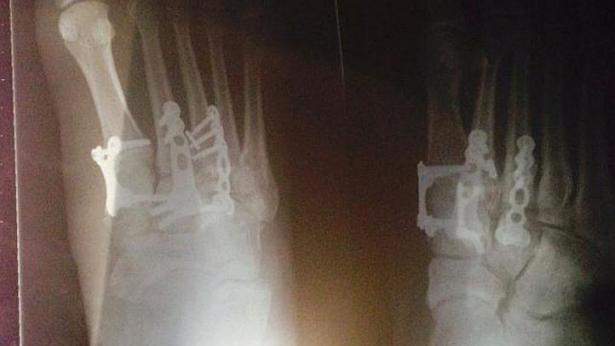

| Tình trạng thương tật của cô Erin Croker |

Người kiện là Erin Crocker, 36 tuổi, làm y tá, sinh sống tại Melbourne. Sự việc trên xảy ra khi cô Erin đang trên chuyến bay từ Thái Lan về Melbourne hôm 4/4 năm ngoái sau kỳ nghỉ lễ. Máy bay gặp luồng xoáy nên rung lắc khiến cô bị ngã xuống sàn. Sau đó, một tiếp viên hàng không cũng mất thăng bằng và ngã lên người cô, dẫm lên chân phải của Erin khiến cô bị thương nặng phải phẫu thuật. Sau cú dẫm chân đó, Eric bị gãy nhiều xương, vết thương sâu làm rách dây chằng khiến cô không thể đi làm trong vài tuần.